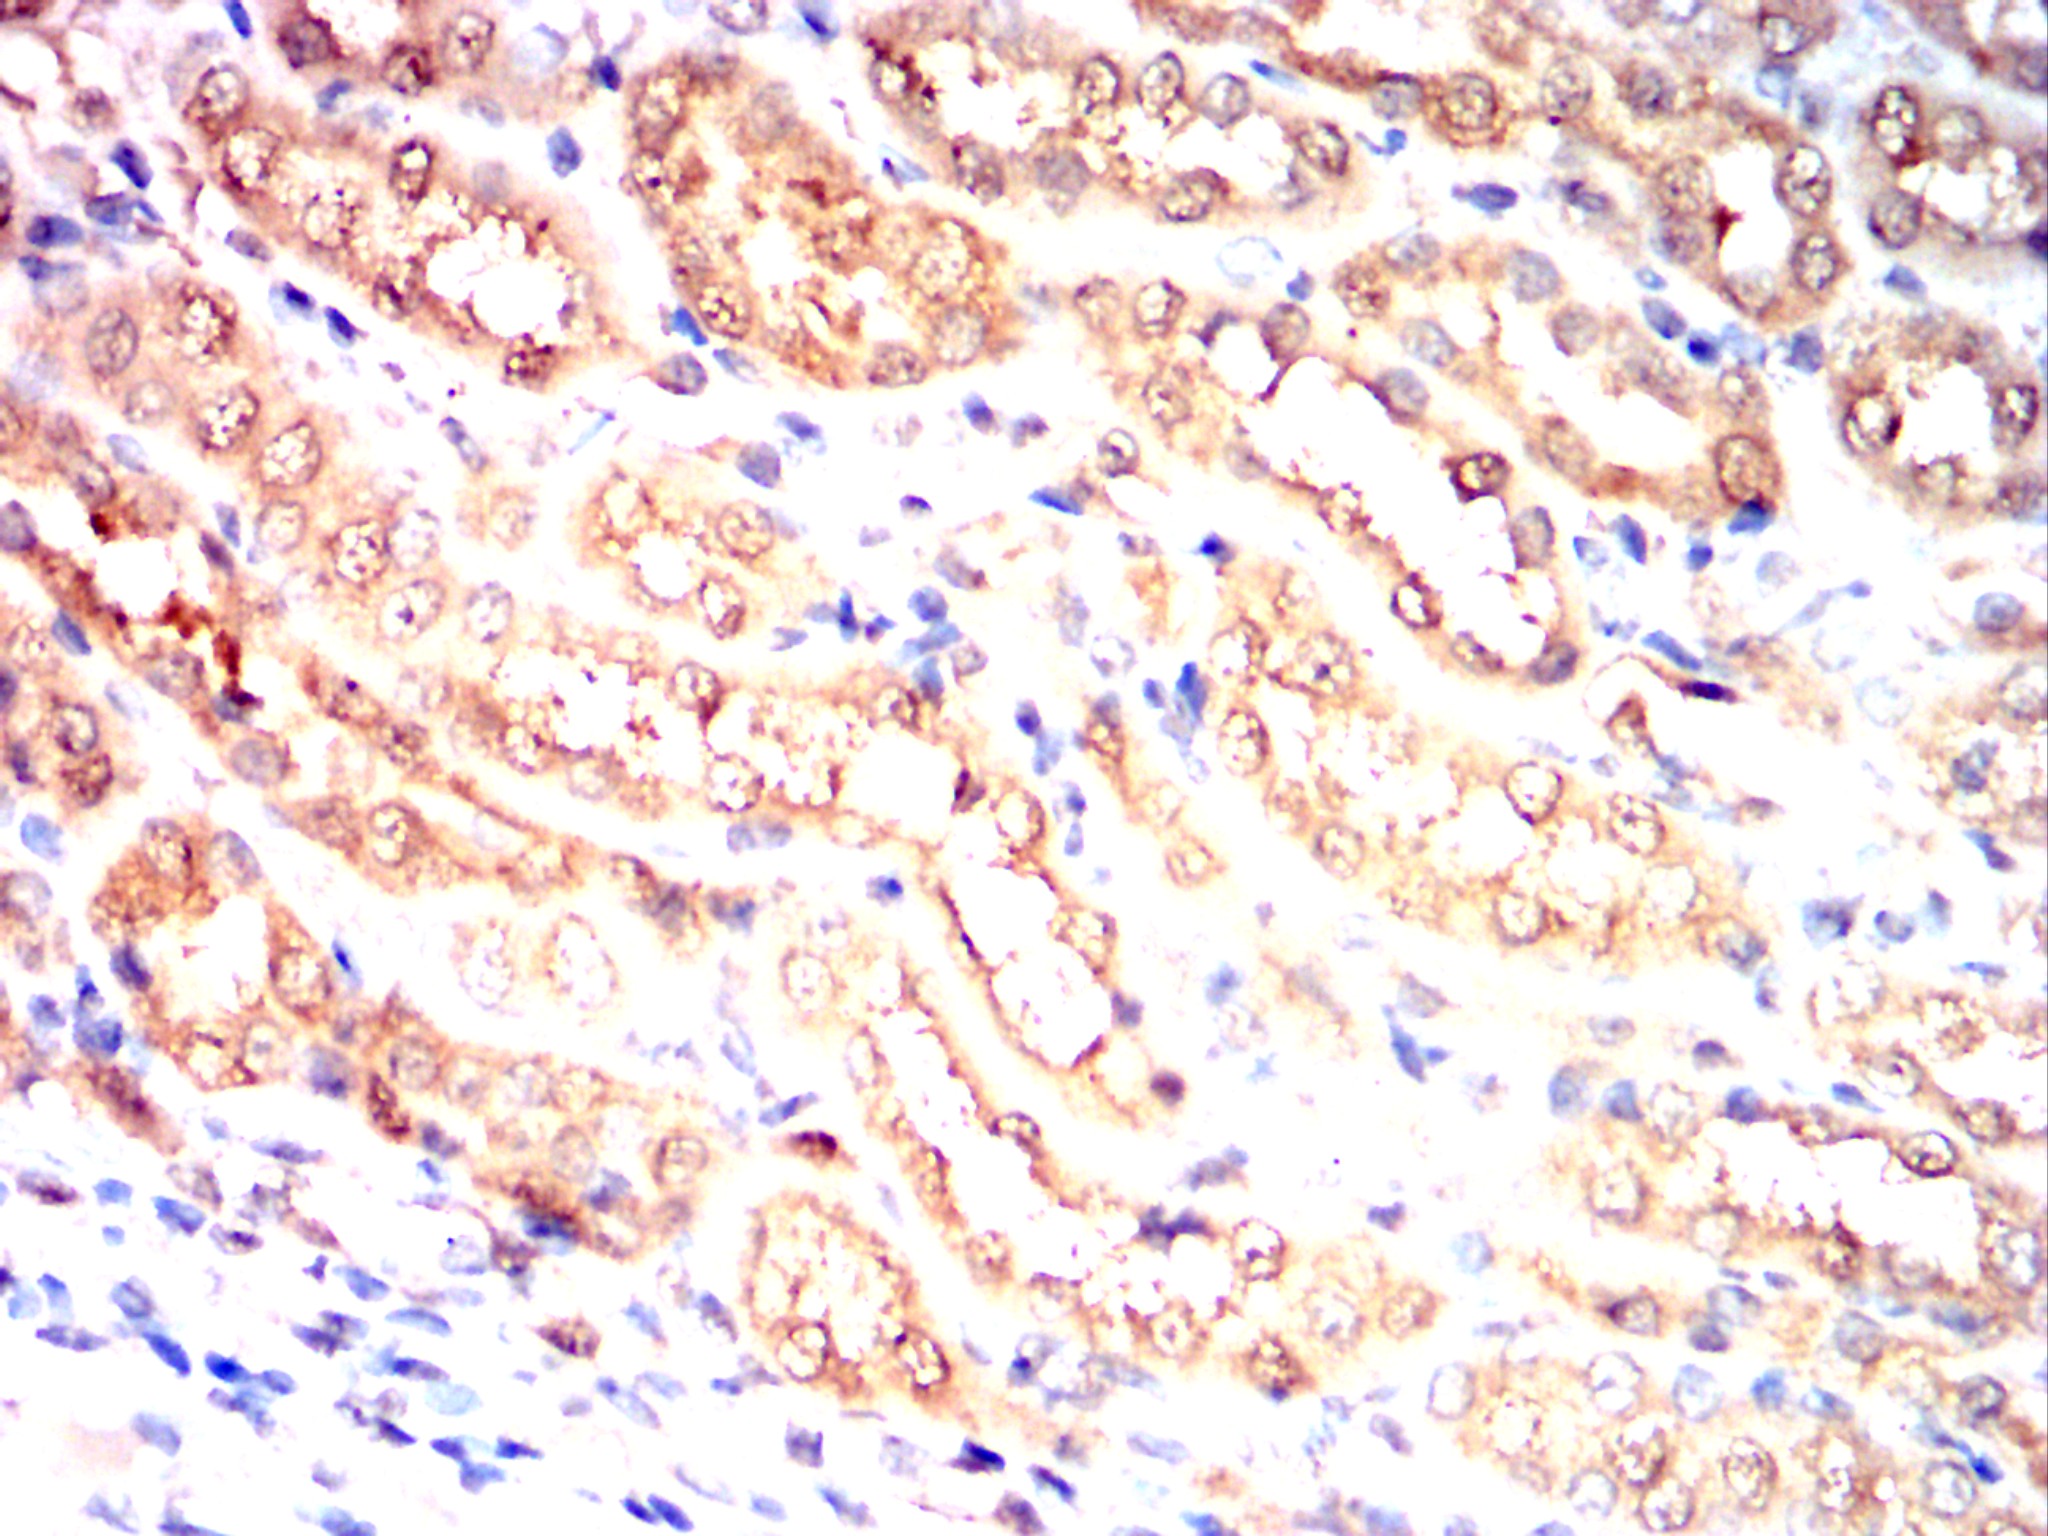

Immunohistochemical analysis of paraffin-embedded Rat kidney using PRKAA2 mouse mAb with DAB staining.